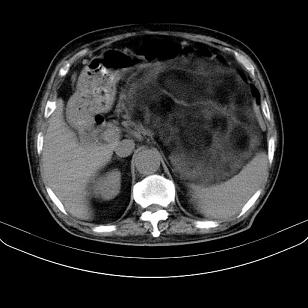

标题: CT21671:男,88岁,左上腹包块 [打印本页]

标题: CT21671:男,88岁,左上腹包块

患者因咳嗽而住院,自觉右上腹包块,无其他不适。

腹膜后高分化脂肪肉瘤

腹膜后脂肪肉瘤

腹膜生占位性病变,脂肪肉瘤可能。

脂肪肉瘤,应测ct值。

支持;后腹膜脂肪肉瘤诊断。

另肠腔扩张及液平,肠梗阻?

左侧腹膜后脂肪肉瘤。

考虑腹膜后脂肪肉瘤可能性大。 畸胎瘤不除外。